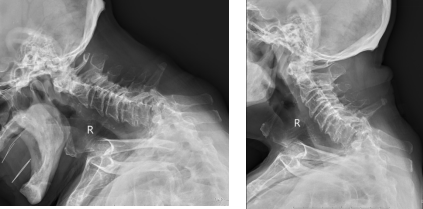

入院后,经过详细检查,老人被确诊为:C7颈椎陈旧性骨折脱位伴右侧小关节交锁、椎体吸收;T1胸椎陈旧性骨折有吸收征。同时,老人还合并高血压病史、肺部感染、心房颤动等多种基础疾病,这使得手术及麻醉风险极大,稍有不慎便可能危及生命。

术前图,患者因骨折疼痛与脊柱畸形,颈部活动明显受限,体态呈现明显异常: